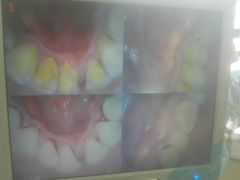

• 赫尔森口腔·牙齿种植修复

• -赫尔森口腔·牙齿种植修复

August0829 | 18-06-10